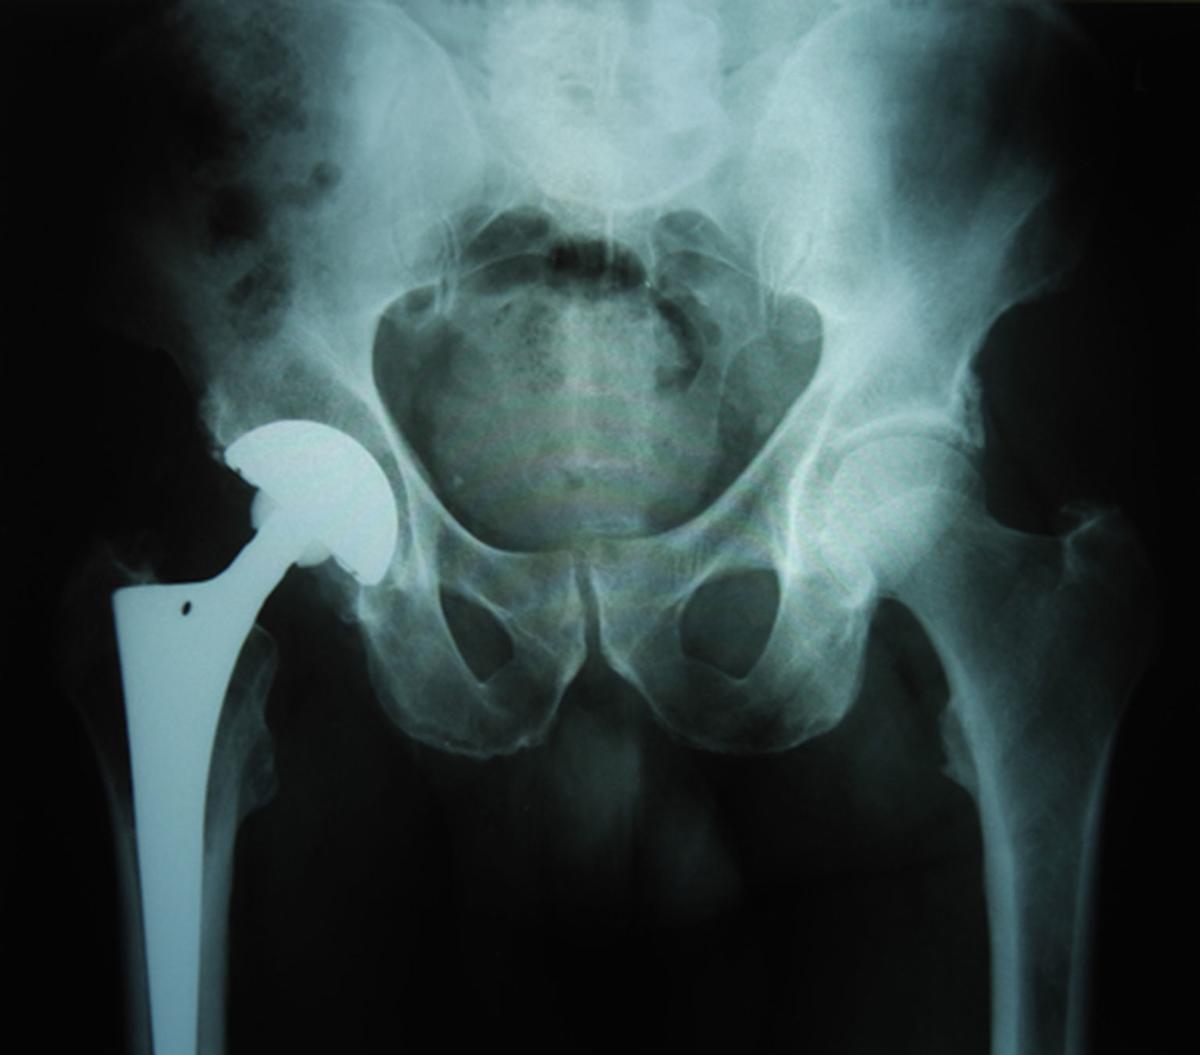

Hip Replacement Mayo Clinic . When hip pain is persistent, limits mobility or makes it difficult to do normal daily activities, hip replacement can be a reasonable. Many people who have hip replacement surgery at mayo clinic can go home the same day. A total hip replacement can reduce pain and improve your quality of life, range of motion, ability to walk or run, and enhance or help you regain. The one you mention — the direct anterior approach — is an option that. I am having a total right hip replacement in six weeks. Hip replacement surgery can be done several ways. Mayo clinic researchers have studied ways to reduce blood loss, control pain and speed recovery for people who undergo hip. My surgeon leaves me to believe that i will be up and around in a few.

A total hip replacement can reduce pain and improve your quality of life, range of motion, ability to walk or run, and enhance or help you regain. Many people who have hip replacement surgery at mayo clinic can go home the same day. Mayo clinic researchers have studied ways to reduce blood loss, control pain and speed recovery for people who undergo hip. Hip replacement surgery can be done several ways. My surgeon leaves me to believe that i will be up and around in a few. I am having a total right hip replacement in six weeks. The one you mention — the direct anterior approach — is an option that. When hip pain is persistent, limits mobility or makes it difficult to do normal daily activities, hip replacement can be a reasonable.